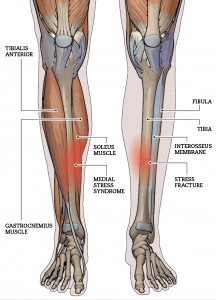

• Shin SplintsShin Splints

• Shin splints is an easy one to explain as pretty much everyone has either had them or knows someone who has.  In the Construct Health clinics we typically see shin splints at the start of the summer or winter sporting seasons as training loads increase and in some people this is the first warning sign of too much too soon.

• The pain presents as a dull ache in the shin following running or other loadbearing exercise.  At first, the symptoms disappear following a good warm-up but over time if not treated it can become a constant pain, occasionally symptomatic of a stress fracture.

• Shin splints are an overuse injury where training load exceeds the body’s’ capacity to adapt.  The tibialis anterior, the tibialis posterior and the connective tissue surrounding the shin (the anchor point for these muscles) become overworked, suffering extensive microtrauma leading to pain and inflammation.  It’s worth noting that stress and microtrauma are the stimuli by which fitness improves and muscles grow and adapt.  However, this mechanism is reliant upon rest and recovery – when the load, whether acutely or cumulatively, exceeds the ability to recover injury ensues.

• Stress FractureShin Stress Fracture

• The lower limb stress fracture is the far end of the spectrum described in the shin splints section.  It shares the same causes, many of the same risk factors and much of the same treatment.  They most commonly occur in the tibia bone of the shin; and the navicular and metatarsal bones of the foot.